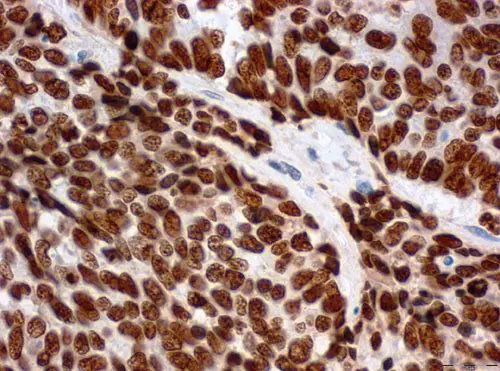

Querschnitt durch eine Gewebeprobe eines Gebärmutterhalstumors. Die Krebszellen enthalten hohe Mengen an LEDGF-Protein (braune Färbung).

Auch in Gewebeschnitten von HPV-positiven Gebärmutterhalstumoren und deren Vorstufen fanden die Forscher höhere LEDGF-Konzentrationen als in gesundem Gewebe. Aber heißt das auch, dass hohe LEDGF-Konzentrationen tatsächlich vor DNA-Schäden schützen? Dafür behandelten die Wissenschaftler HPV-positive Gebärmutterhalskrebszellen mit DNA-schädigenden Chemikalien oder Gammastrahlen. „Wenn wir in den Krebszellen LEDGF blockiert haben, entstanden deutlich mehr DNA-Schäden und die Zellen teilten sich weniger“, berichtet Studienleiter Professor Felix Hoppe-Seyler. „Aus diesen Versuchen schließen wir, dass HPV die Produktion von LEDGF mithilfe ihrer Gene E6 und E7 aktivieren und Krebszellen so vor DNA-Schäden bewahren.“

Bildunterschrift: Querschnitt durch eine Gewebeprobe eines Gebärmutterhalstumors. Die Krebszellen enthalten hohe Mengen an LEDGF-Protein (braune Färbung).

Quelle: Miriam Reuschenbach, Universitätsklinikum Heidelberg